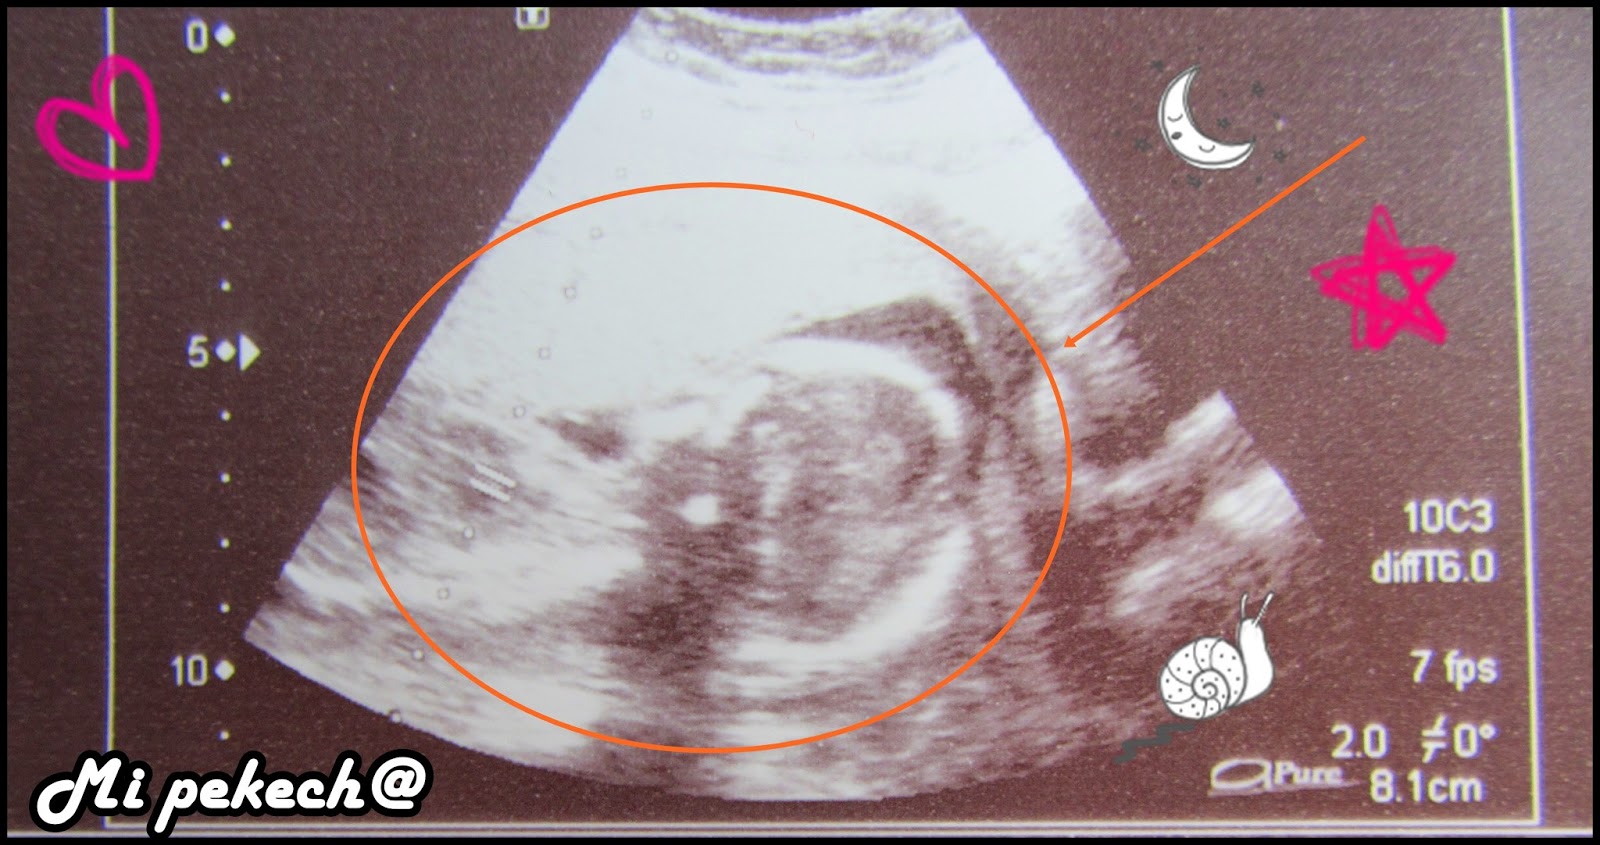

WebLa primera ecografía que se realiza a una embarazada ofrece datos muy interesantes sobre la gestación, aunque el embrión sea minúsculo. Detallamos a continuación los elementos que se identifican en las primeras ecografías, así como las etapas de. WebEsta semana tu bebé tiene el tamaño de un nabo pequeño. Ya mide casi 13 centímetros (5 pulgadas) y el cordón umbilical, por donde come y respira, está cada día más grueso y. WebEcografía de la semana 17 de embarazo: embrión de perfil. Se visualiza la órbita, la nariz y la boca. Asimismo se visualiza una parte del abdomen y la placenta arriba de la imagen.. WebA las 17 semanas de embarazo, una mujer debe visitar a un ginecólogo y pasar las pruebas necesarias. Incluyen pruebas de sangre y orina, pruebas hormonales. En la recepción,. WebEntre la semana 17 y 19 del embarazo verás a tu bebé crecidito: mide unos 15 centímetros y pesa alrededor de 200 gramos. Sus movimientos son cada vez. WebAbout Press Copyright Contact us Creators Advertise Developers Terms Privacy Policy & Safety How YouTube works Test new features Press Copyright Contact us Creators ... WebEl ecocardiograma fetal inicial suele realizarse entre las semanas 18 y 22 de gestación y puede repetirse según sea necesario a lo largo del embarazo. El estudio inicial suele.

WebAbout Press Copyright Contact us Creators Advertise Developers Terms Privacy Policy & Safety How YouTube works Test new features Press Copyright Contact us Creators ... WebEl ecocardiograma fetal inicial suele realizarse entre las semanas 18 y 22 de gestación y puede repetirse según sea necesario a lo largo del embarazo. El estudio inicial suele. WebEn la semana 17 de embarazo el feto alcanza un tamaño medio entre 12-16 cm, y un peso aproximado de 100 gramos. PUBLICIDAD. La posición habitual es semiflexionada, con.